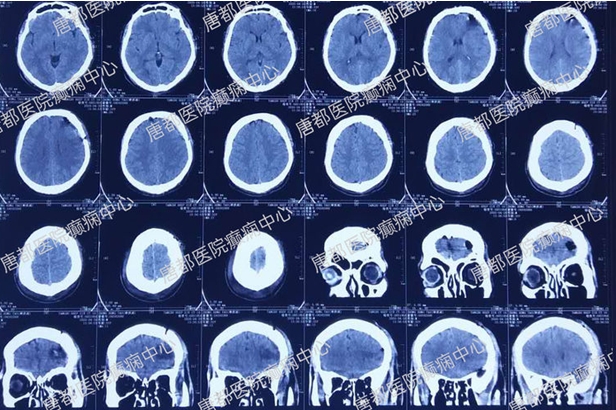

术后CT检查:

术后3个月无发作。